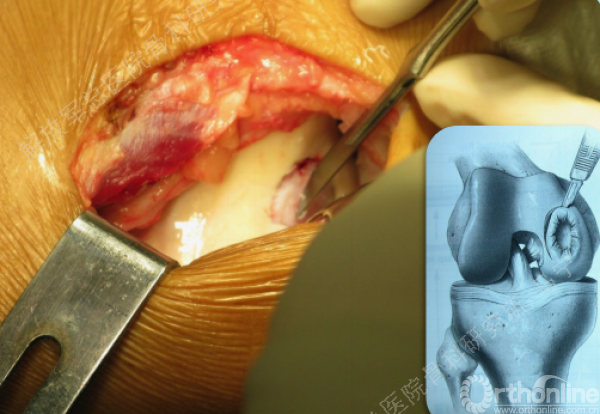

组织工程软骨植入:第二次手术-组织工程软骨回植。

手术切口:根据软骨损伤部位来确定手术切口入路。

术中所见和影像检查一致。

软骨损伤区的清创。

软骨缺损范围的测量。

复位后屈伸膝关节,观察补片情况。

上图是我们院自主研发的以软骨细胞外基质为原料的孔隙取向性支架。可以做成任意厚度任意大小,按照软骨缺损的形状裁剪好以后。这个损伤面积大概在4平方厘米左右。